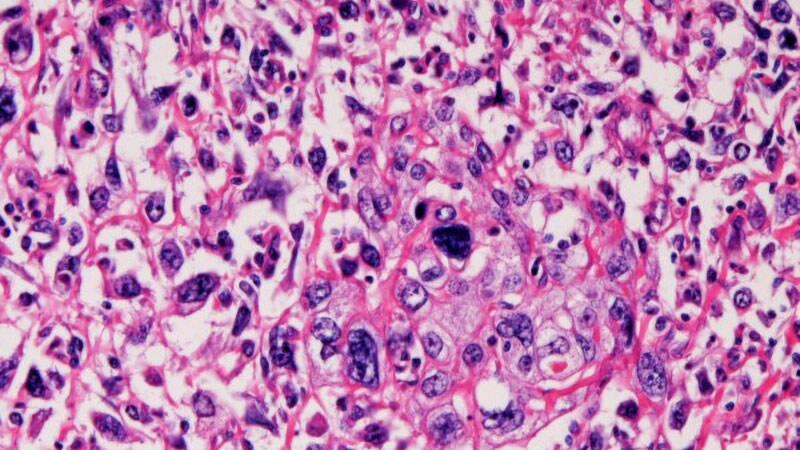

Bladder Cancer